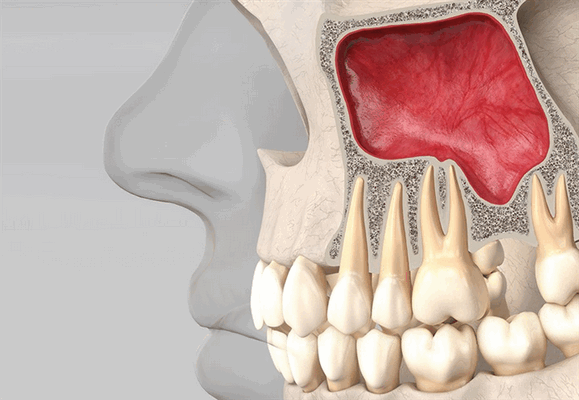

Синус-лифтинг проводят при сильной атрофии челюстной ткани. Обычно процедуру проводят на верхней челюсти при продолжительном отсутствии одной или нескольких жевательных зубов.

Верхняя челюсть

В большинстве случаев если высота костной ткани верхней челюсти менее 8 мм, проводится закрытый синус-лифтинг. После откидывания десневого лоскута стержень фиксируют в кортикальной пластинке (дистальный отдел) или в дне полости носа (передний отдел). Такое положение обеспечивает лучшую первичную стабильность.

Благодаря проведению разреза по альвеолярному гребню хорошо видно носонебный канал и срединный шов неба, что позволяет избежать повреждения носовой полости или гайморовых пазух.

- Срок и причина утраты зубов. Это поможет подобрать наилучший тип импланта. Если зуб отсутствовал долго, может потребоваться синус-лифтинг.